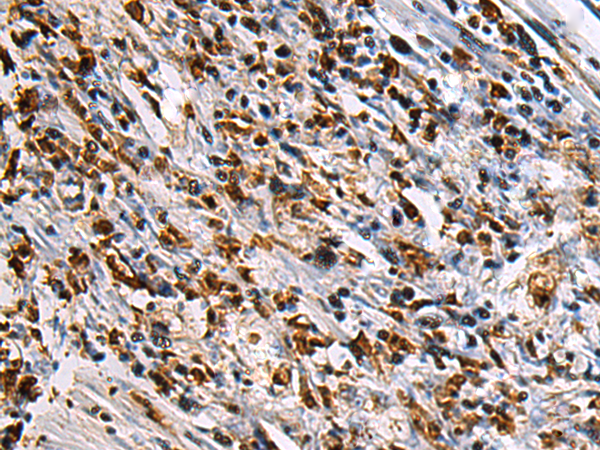

IHC positive control:

Human brain and Human gastric cancer

IHC Recommend dilution:

100-300